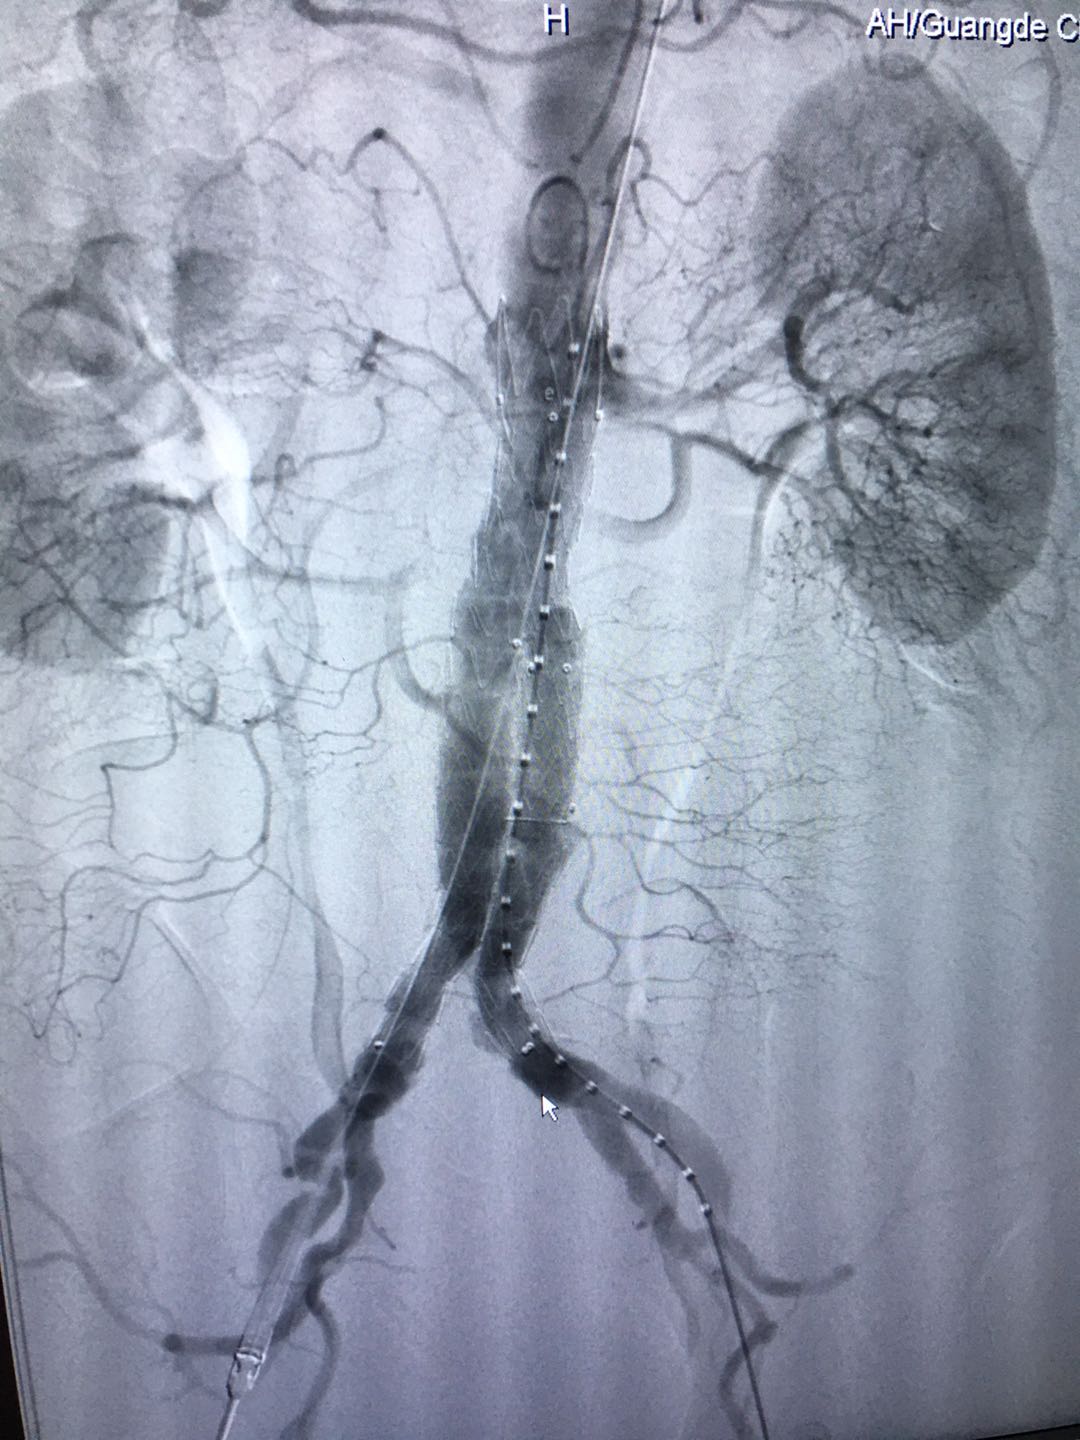

近日,普外二科成功完成一例腹主动脉瘤腔内隔绝术加腹腔镜下乙状结肠癌根治术。同一个病人先后两次手术都非常顺利,取得满意效果,患者现已康复出院。这一手术的成功,标志着我院普外科的发展又迈上了一个新台阶。

这位73岁的男性患者,因反复腹部疼痛不适伴稀便,外院行肠镜检查考虑乙状结肠肿瘤,为求进一步治疗入住我科。然而,在术前检查中,却意外发现比结肠癌更为棘手的是,腹膜腔CT检查发现患者患有腹主动脉下段动脉瘤。腹主动脉瘤就像人体不定时“炸弹”,大多数平时没有症状,但是一旦破裂,患者可能出现剧烈腹痛、低血压、大出血,病情极其凶险,在短时间内患者就会出现死亡。主治医生李文明主任认为一期行乙状结肠癌根治术相对风险较高,和弋矶山医院司春强主任商议后,决定先拆除这个不定时“炸弹”,再安排结肠癌手术。

7月18日,在我院导管室,患者在全麻下,经双侧腹股沟小切口,在动脉造影(DSA)监测下,实施腹主动脉瘤腔内隔绝术,术中出血少,创伤小,治疗一周后患者痊愈出院。